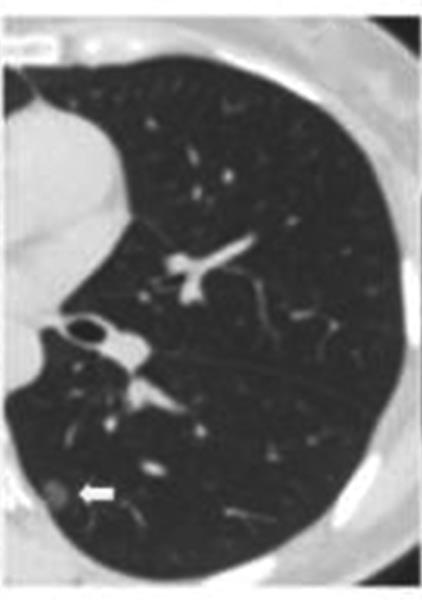

• 纯磨玻璃结节肺腺癌CT征象与其浸润程度的相关性分析及预测模型构建

2023, 48(4):423-429. DOI: 10.13406/j.cnki.cyxb.003200

摘要 (138) HTML (44) PDF 1.10 M (286) 评论 (0) 收藏

摘要:目的 探究纯磨玻璃结节(pure ground-glass nodule,pGGN)肺腺癌计算机断层扫描(computed tomography,CT)征象与其浸润程度的相关性,建立CT征象与浸润程度的预测模型。方法 回顾性分析424例经手术切除、病理活检证实且胸部CT表现为pGGN的肺腺癌患者临床资料及CT征象,根据病理活检结果分为非典型腺瘤样增生、原位腺癌、微浸润腺癌和浸润性腺癌4组,对组间差异采用卡方检验或Fisher确切概率法进行统计分析。对有统计学意义的结果,使用怀卡托智能分析环境(Waikato environment for knowledge analysis,WeKa)中的6种学习算法进行预测模型构建,并验证准确性,挑选出最适用于本研究的预测模型。结果 4组间在结节直径、结节密度值上的差异具有统计学意义(P<0.001),对应的直径平均值分别为6.90、8.65、10.71、14.56 mm,对应的密度平均值分别为-633.16、-543.04、-401.03、-322.94 HU,随着病灶的浸润程度加重,结节的直径及密度值呈现明显的上升趋势。4组间在结节边界、分叶、毛刺、血管穿行、胸膜凹陷、空气支气管征、空泡征等的差异具有统计学意义(P<0.05),而结节的生长位置,年龄、吸烟史、直系亲属肺癌家族史等差异无统计学意义(P>0.05)。随机森林算法所构建的模型预测准确率为76.42%~79.72%,Kappa系数为0.597~0.670,受试者工作特征(receiver operating characteristic,ROC)曲线下面积均大于0.9,在误差指标中表现最优,是最适合于本研究的预测模型。结论 pGGN的不同CT征象与其浸润程度密切相关,可以用于建立预测模型。基于随机森林算法所建模型,在有创干预前早期快速识别pGGN浸润程度的平均准确率为78.07%,准确度最高,对肺癌预测具有潜在应用价值。

• 0+1

• 1+1

• 2+1

• 3+1

• 4+1